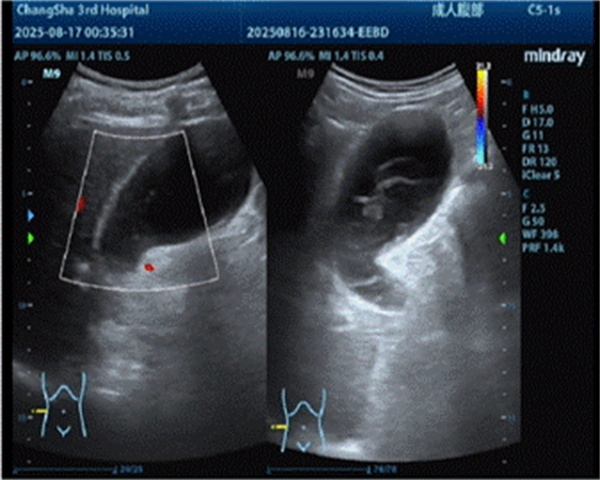

术前超声

入院紧急评估及权衡后,医护团队决定行超声引导下经皮肝胆囊穿刺造瘘术引流出脓性胆汁,为老人缓解症状。可好景不长,穿刺几天后由于胆汁浓稠、胆泥形成导致引流管不通畅,彭爹爹再次出现发热及右上腹疼痛,引流量减少的情况。